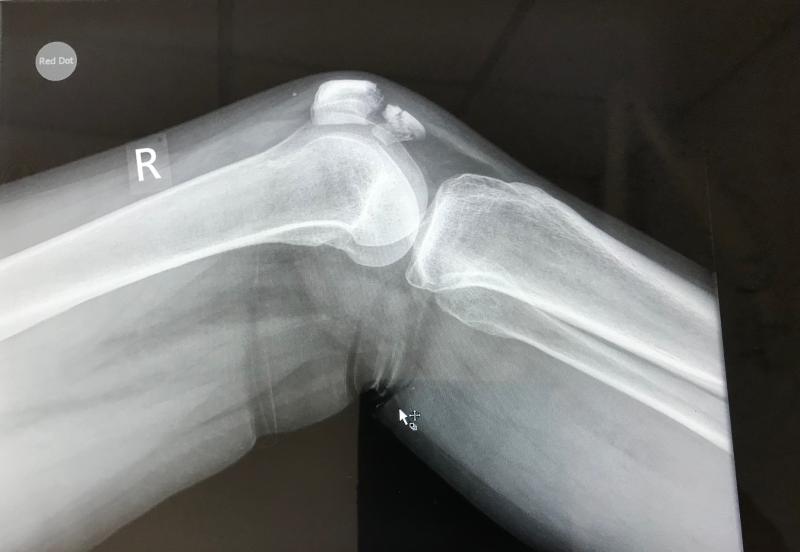

Tanı Yöntemleri Diz kapağı çatlağının tanısı, klinik muayene ve görüntüleme teknikleri ile konulmaktadır. Tanı sürecinde kullanılan başlıca yöntemler şunlardır:

Diz Kapağı Çatlağı Belirtileri ve Tedavisi

Diz kapağı çatlağı, diz ekleminde patella yüzeyinin hasar görmesiyle ortaya çıkan bir durumdur. Genellikle travma, aşırı kullanım veya yaşa bağlı değişikliklerden kaynaklanır. Belirtileri arasında ağrı, şişlik ve hareket kısıtlılığı bulunur. Erken tanı ve tedavi ile yönetilebilir.

Diz kapağı çatlağı, diz ekleminde yer alan diz kapağının (patella) yüzeyindeki kemik yapısının hasar görmesiyle oluşan bir durumdur. Bu durum, genellikle travma, aşırı kullanım veya dejeneratif değişiklikler sonucunda meydana gelir. Diz kapağı çatlağı, sporcular ve fiziksel aktiviteye katılan bireyler arasında yaygın olarak görülse de, yaşa bağlı değişiklikler sonucu da ortaya çıkabilir. Bu makalede, diz kapağı çatlağının belirtileri, tanısı ve tedavi yöntemleri detaylı bir şekilde ele alınacaktır. Belirtiler Diz kapağı çatlağının belirtileri genellikle aşağıdaki gibidir: